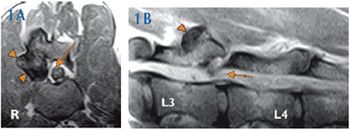

A 10-year-old 8.6-lb (3.9-kg) spayed female domestic medium-haired cat had been evaluated by the referring veterinarian because of lethargy, right pelvic limb lameness, lumbar discomfort, reluctance to jump, and tail weakness.